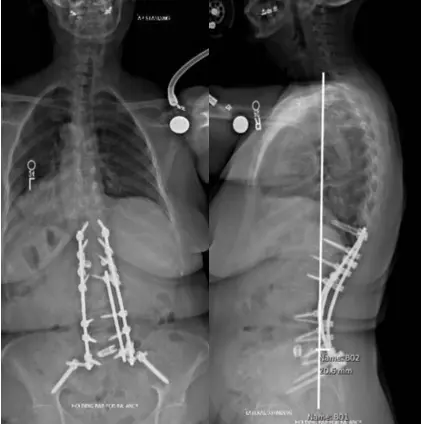

scoliosis xray

Treatment: T11-ilium posterior instrumented arthrodesis, L2-S1 Smith-Petersen

osteotomies, and L5-S1 discectomy with interbody fusion

Smith used surface anatomic landmarks and a high-speed drill to place instrumentation and, with fluoroscopy guidance, drilled starter holes into the bone for the pedicle screws. A pedicle finder was used to cannulate the trajectories. Screws were placed bilaterally spanning from T11 through S1, and supportive bolts were placed into the ilium. Osteotomies provided decompression of the spinal canal and the exiting nerve roots, and helped release and correct the scoliosis.

At L5-S1, Smith performed a discectomy to allow placement of a titanium interbody spacer, as a means of deformity correction and an aid for bone healing across the lumbar-sacral junction. Cobalt chromium rods were then measured, cut, contoured and placed to span from T11 through the ilium bilaterally. Locking caps were placed over the heads of the screws to secure the rods, and a junctional tether was placed at the top of the construct for proximal junctional support.